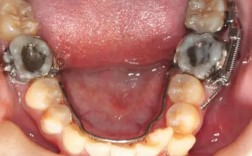

- 口内支抗:如Nance弓(利用腭部黏膜组织增强支抗)、腭杆(连接两侧磨牙,防止近中倾斜)、舌弓(下颌牙弓内增强支抗)。